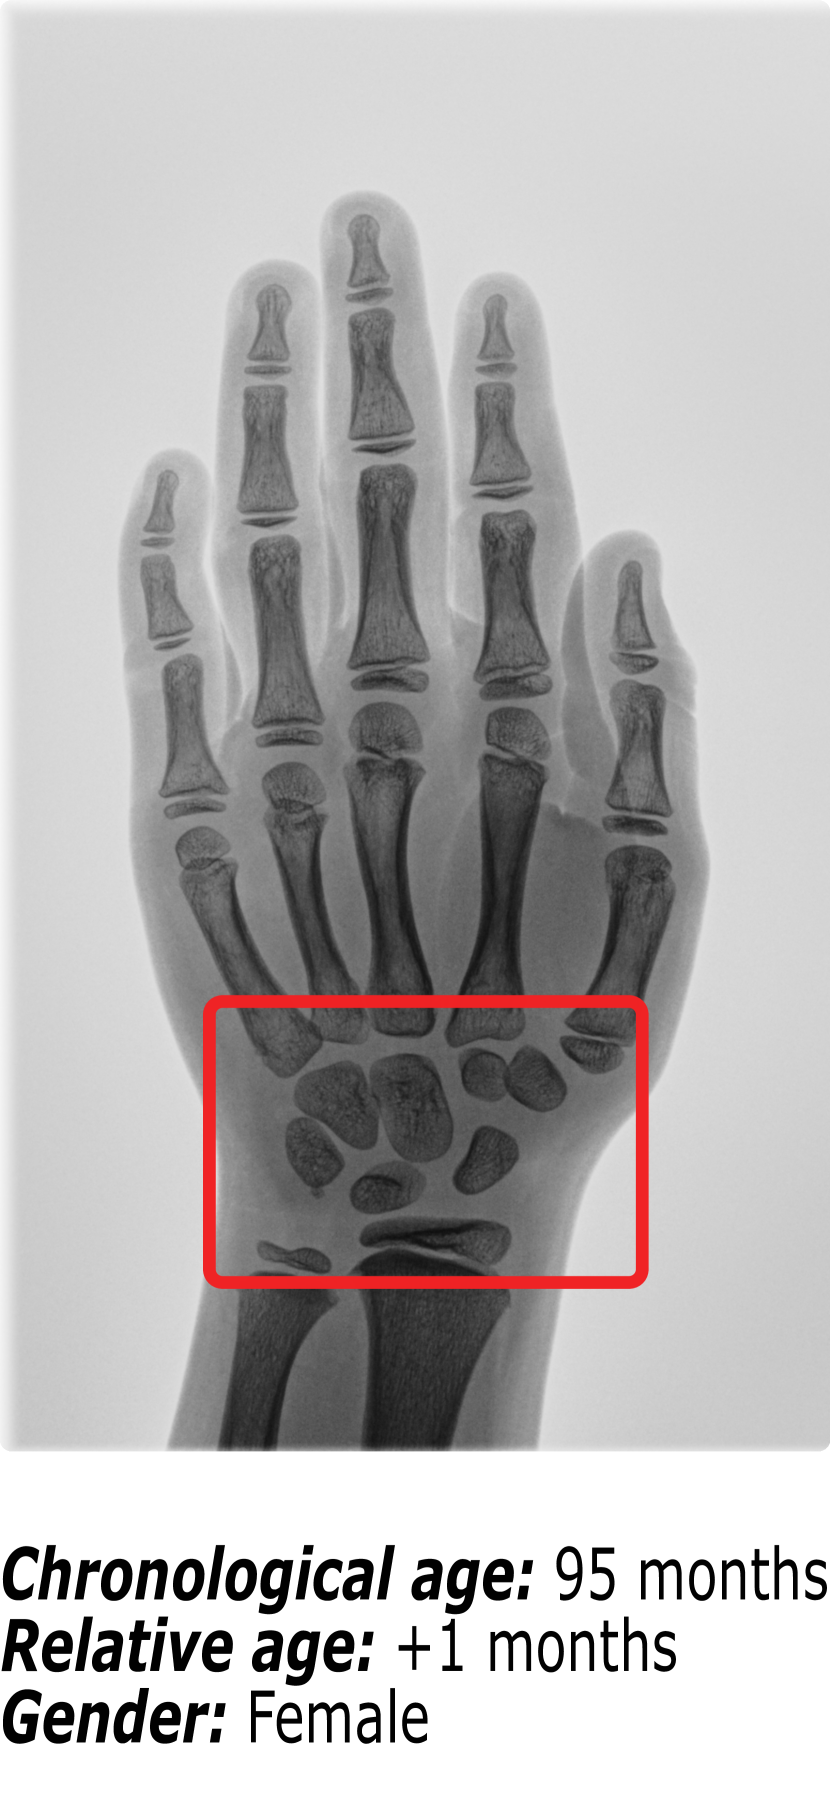

Figure 1 shows an example of the influence that identity markers have on bone age. The three hand radiographs present in Figure 1 belong to children with virtually the same chronological age. However, it is visible that the ossification patterns present in each of the hand radiographs vary significantly. First, gender is an important identity marker to take into account. Comparing Figure 1(b) (a female patient) and Figure 1(c) (a male patient), it is possible to observe that the bone structures in the region surrounded by the red box are more developed for the female than for the male. This finding is supported by the fact that skeletal development is faster in females than in males.

Nonetheless, when comparing two hand radiographs of patients of the same gender with the same chronological age, as it happens between Figure 1(a) and Figure 1(b), the expected result would be that the bone patterns did not vary much. Because most patients have a regular growth pattern, physicians use the chronological age as a starting point and compute the difference in skeletal development. This relative bone age between the patient’s chronological age and the patient’s bone age is the information that the radiologists use to diagnose growth disorders. However, Figure 1(b) belongs to a patient with regular growth, having a relative bone age of +1 month, while Figure 1(a) belongs to a patient with accelerated growth, hence the relative bone age of -38 months.